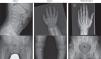

La serie esquelética muestra en ambos osificación retardada de epífisis y metáfisis e irregularidad a nivel de huesos largos, cabeza femoral y acetábulo (fig. 2). En la mano se observan huesos del carpo y metacarpo cortos, falanges con epífisis en forma de cono y metáfisis irregulares. Destacan cuerpos vertebrales con «lengüetas» anteriores. Se realiza analítica sanguínea que resulta sin alteraciones. Se considera el diagnóstico diferencial entre PSACH, acondroplasia, MED y mucopolisacaridosis tipo IV.

Figura 2.

Casos 1 y 2: cuerpos vertebrales con «lengüetas» anteriores; huesos del carpo y metacarpo cortos e irregulares, falanges con epífisis en forma de cono; irregularidad de huesos largos, cabeza femoral y acetábulo. Padre del caso1: radiografías de mano y pelvis compatibles con la normalidad.